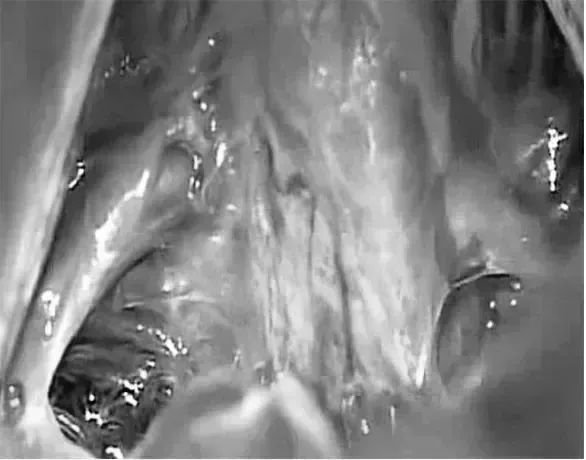

術(shù)中照片顯示Galenic靜脈引流通過小腦上蚓,小腦左側(cè)旁入路暴露的路線